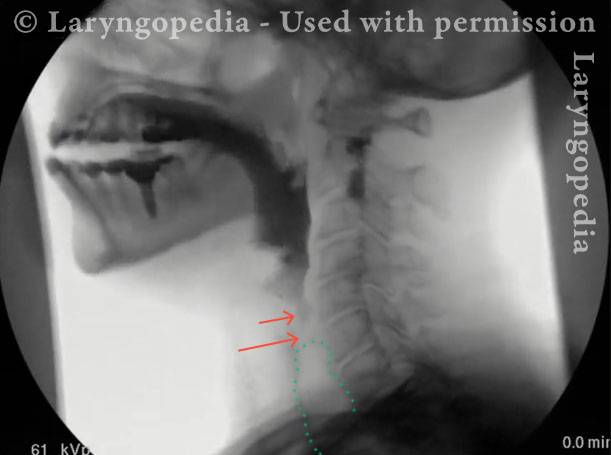

This visual series depicts a hallmark feature of R-CPD: marked dilation of the upper esophagus filled with swallowed and retained air. Normally, this air would be burped out, but in persons with R-CPD, it cannot be expelled.

The retained air can push upward, creating a sense of pressure and a distinct gagging or “throat nausea” sensation. It also explains a striking procedural observation: during office upper esophagoscopy, air insufflation is unnecessary, because the patient’s esophagus is already dilated by trapped air, allowing visualization of its walls.

Retained Air in Larynx (2 of 4)